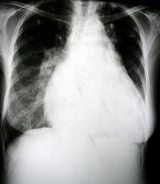

Hipertansiyon gibi kronik rahatsızlıklara bağlı mevcut kalp hipertrofisi veya kalp krizi öyküsü, kalp yetmezliğinde en önemli etmendir. Bu tür rahatsızlıklar kalbe zarar verdikten sonra, kardiyomiyosit denilen kalp kası hücreleri, vücut yanıt vermeye çalıştıkça büyür ve bu da kalp büyümesine neden olur.